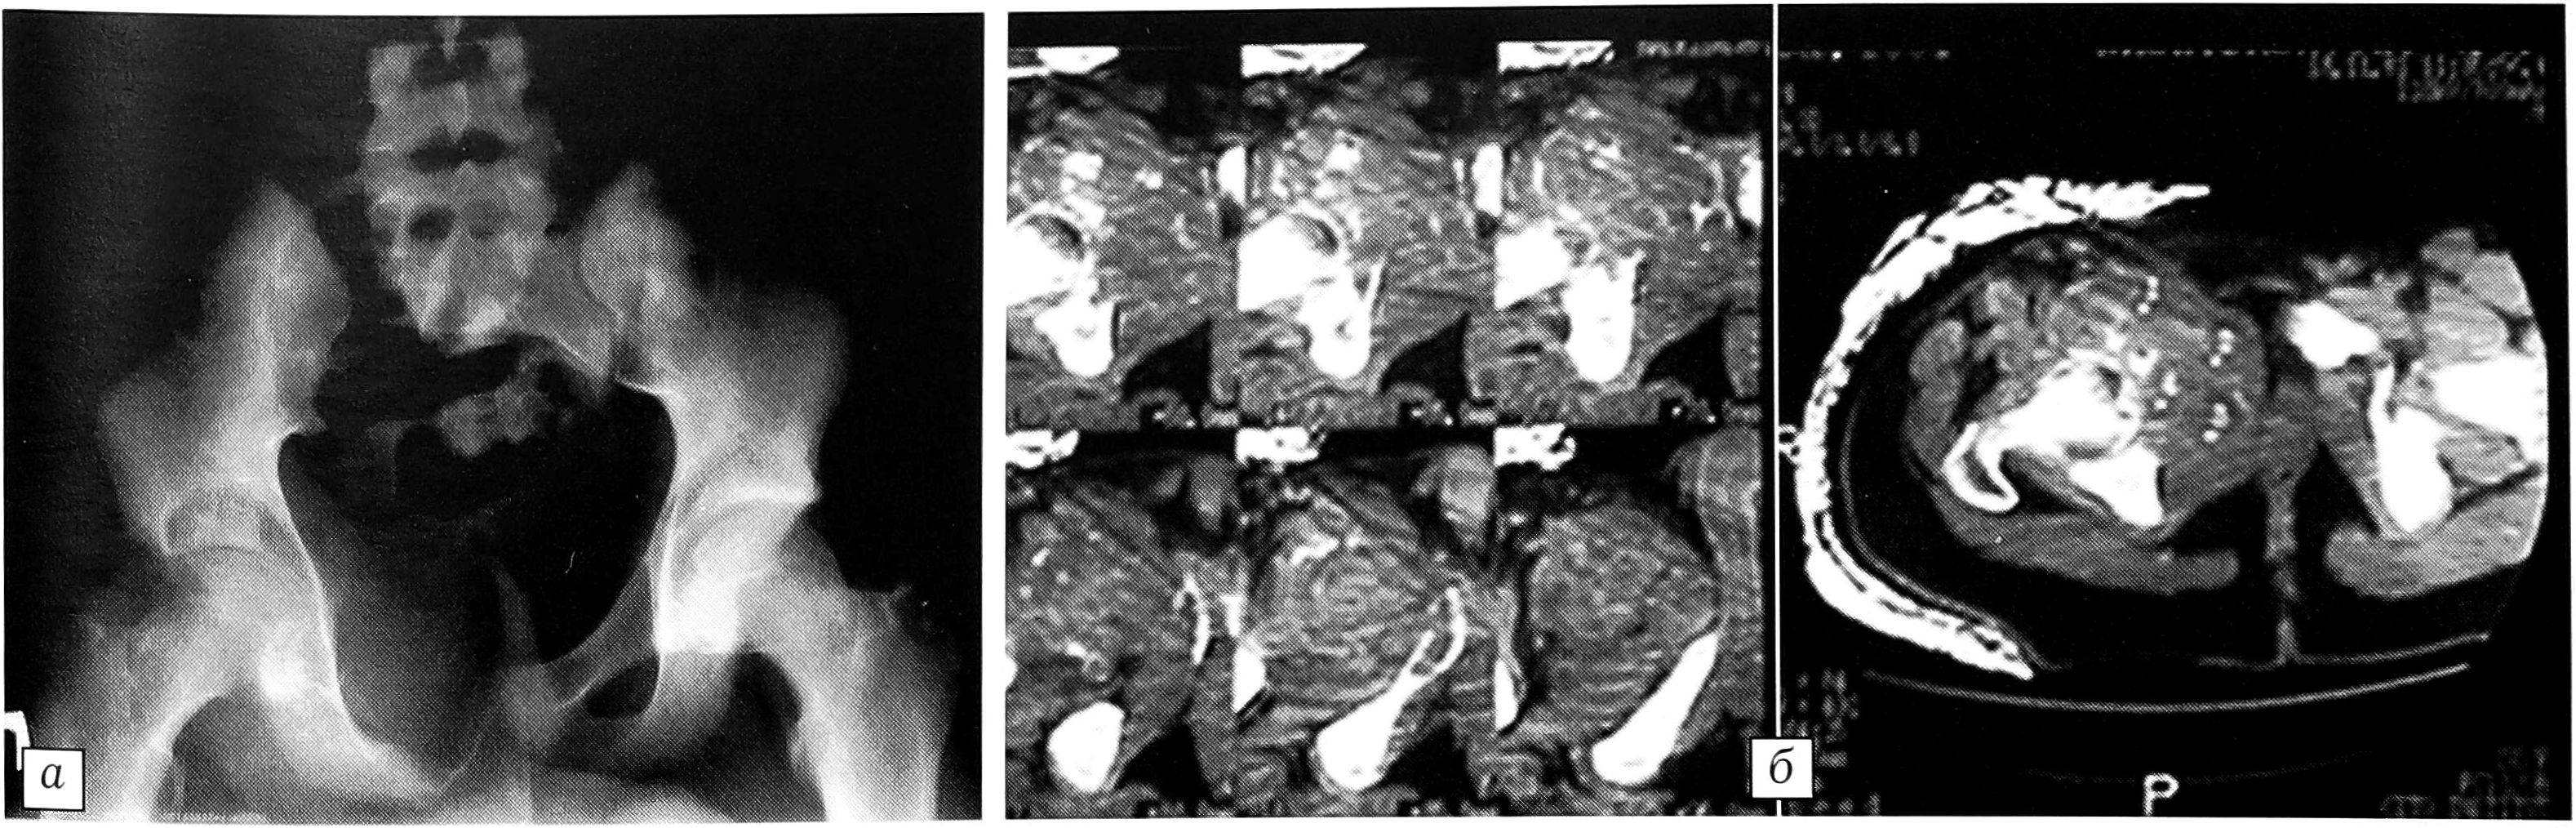

Через 1 мес у пациента появились жалобы на болезненное мочеиспускание. Клинически определялось увеличение образования в правой лонной области, увеличение паховых лимфатических узлов, которые были подвижны и безболезненны. Рентгенологически отмечено прогрессирование процесса: увеличение остеолитического очага деструкции и мягкотканного компонента с вовлечением тела подвздошной кости. Суставная поверхность вертлужной впадины местами была разрушена. Мочевой пузырь смещен кнутри, инфильтративного роста в нем не выявлено (рис. 2). Произведена рентгенография легких — данных, указывающих на метастазы, не обнаружено. Показатели общего анализа крови оставались в норме. Пересмотрены гистологические препараты — признаков злокачественного процесса не выявлено.

Рис. 2. Рентгенограмма таза (а) и компьютерная томограмма (б) через 1 мес: отмечается прогрессирование патологического процесса.